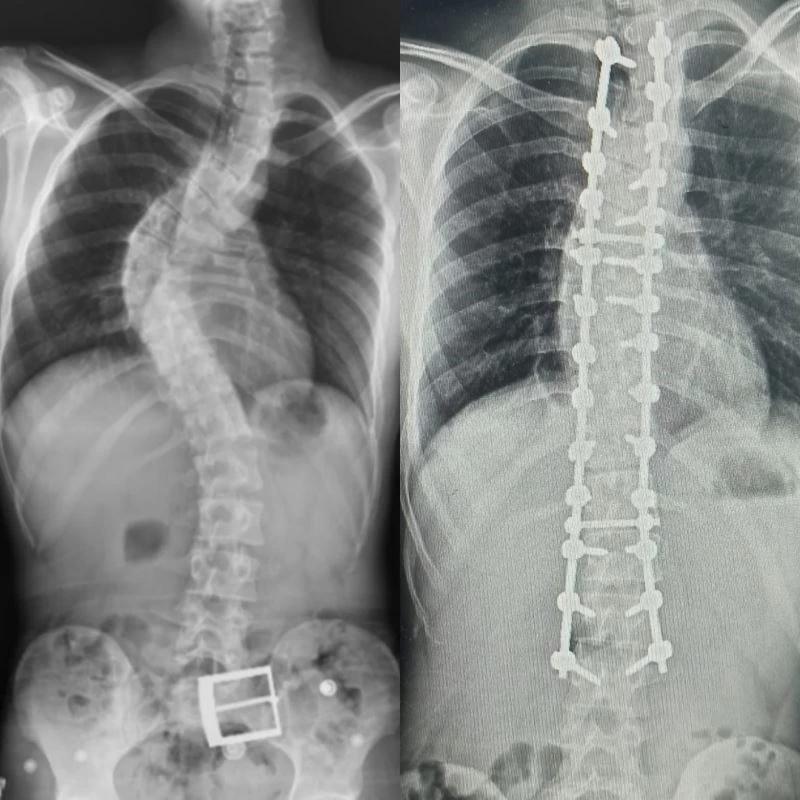

Sırt ağrıları, omurga eğriliği ve kamburlaşması olan 20 yaşındaki hasta Ahmet Akan, Tokat’tan Samsun’a gelerek ameliyat oldu. 7 saat süren ameliyat sonunda Ahmet Akan sağlığına kavuştu.

Yapılan muayene ve incelemeler sonucu hastada 73 derece skolyoz (omurga eğriliği) ve kifoz (kamburluk) tespit edilerek Ahmet Akan’a ameliyat önerildi. Samsun Üniversitesi Tıp Fakültesi Ortopedi ve Travmatoloji Anabilim Dalı Öğretim Üyelerinden Dr. Öğr. Üyesi Ömer Bozduman, deneyimli ameliyat ve anestezi ekibi eşliğinde görev yaptığı Samsun Eğitim ve Araştırma Hastanesi’nde 7 saat süren başarılı bir skolyoz ameliyatı gerçekleştirdi.

Hasta ile ilgili bilgi veren Dr. Öğretim Üyesi Ömer Bozduman, “Hastamız artan sırt ağrıları ve omurga eğriliğinin ilerlemesi şikâyetiyle kliniğimize başvurdu. İnceleme ve değerlendirmelerimiz sonucu ameliyat kararı verdik. 7 saat süren skolyoz ameliyatını takiben 12 saat sonra hastamız kaldırılıp yürütüldü. Ameliyat sonrası nörolojik olarak hiçbir sorunu yok. Eğriliği tamamen düzeldi, boyu uzadı. Şu an kendisi yürüyüp gezebiliyor. Hastayı 5 gün sonra taburcu edip evine gönderiyoruz. Her ameliyatta olduğu gibi skolyoz ameliyatlarında da ekip çalışması çok önemlidir. Uzun süren bu ameliyatı, hastanemizin özverili ameliyat ve servis hemşireleri ve deneyimli anestezi ekibi ile gerçekleştirdik” dedi.